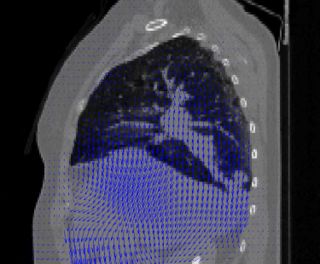

Deformable Registration

Accurate assessment of radiation dose to the thorax and abdomen during respiration requires simulation of a static beam that irradiates a moving and deforming target. The goal of this project is to use deformable registration for radiation dose calculations in these sites.